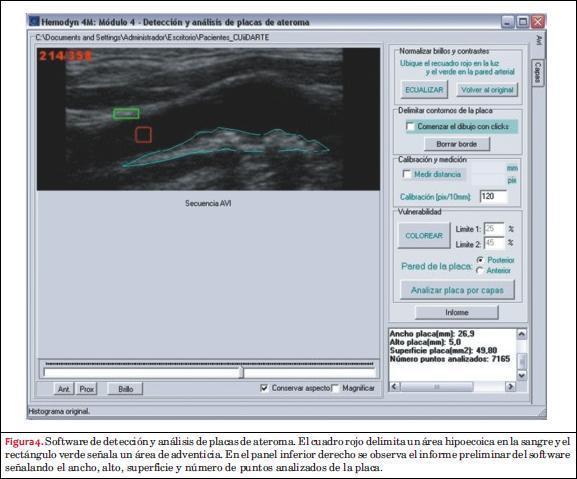

Composición y clasificación de la PAC

En aquellos individuos en los cuales se identificó PAC, se determinó su composición estructural a partir del análisis de los niveles de grises de la imagen ecográfica seleccionada, como se representa en las figuras 4 y 5. La resolución cuenta con 256 niveles de gris (0 = negro; 255 = blanco). El procedimiento de procesamiento de la imagen consiste en desplazar dos volúmenes de muestra, uno rojo y otro verde, dentro del lumen arterial hipoecoico (“referencia sangre”) y otra sobre la pared de la arteria hiperecoica, (“referencia adventicia”), respectivamente (figura 4). Este procedimiento de normalización permite compensar la ganancia del ecógrafo y las diferencias propias de estructura del paciente(32). Mediante la determinación manual a partir de clics de un área de interés, el operador delimita la PAC creando un polígono que la encierra dentro de un contorno. El número de pixeles dentro del contorno se utiliza para estimar el tamaño de la PAC en ese corte ecográfico. El tamaño de cada pixel se aproxima utilizando la calibración del ecógrafo, que resulta para el nivel de magnificación habitual entre 102 y 140 pixeles/cm. A cada pixel de la placa se le asigna un valor (“nivel de gris”) de acuerdo a su ubicación en la escala de grises. Se modifica la imagen a una normalizada según su composición, determinando la MNG de acuerdo a la intensidad global de los pixeles de la PAC(12,13,32).

Con la imagen normalizada de la escala de grises, el software realiza automáticamente un mapeo en tres colores (rojo, amarillo y verde), dependiendo de su valor de la escala de niveles de grises. Los puntos de corte para el rojo, amarillo y verde fueron <50, entre 50-80 y >80, respectivamente(29). Este método determina “áreas rojas” dentro de la PAC, correlacionadas con un contenido hemorrágico o lipídico (ecogenicidad similar a la sangre); “áreas verdes”, correspondientes a una ecogenicidad similar a la adventicia representando contenido fibroso o calcificado; mientras que “áreas amarillas” abarcan el conjunto intermedio de la escala de grises entre las dos anteriores, que representan sectores con contenido fibrolipídico(13).

La clasificación de las PAC según su composición en tres grupos (hipoecogénica = lipídica; = isoecogénica = fibrolipídica; hiperecogénica = fibro/calcificada) se basa en la clasificación propuesta por Polak y colaboradores(53) y fue realizada automáticamente por el software y validada por los operadores. Se definió una PAC como fibrosa/calcificada (FC) o lipídica (L) cuando su estructura se componía de más de 50% por áreas hiperecoicas (“áreas verdes”) o menos de 50% por áreas hipoecoicas (“áreas rojas”), respectivamente. A su vez, se definió como placa fibrolipídica (FL) cuando ninguno de los componentes de las escalas de grises superó el 50%. En la figura 5 se puede observar un ejemplo de cada tipo de PAC a partir del mapeo de colores aportado por el software. Todas las imágenes fueron calibradas de manera protocolizada y estandarizada para permitir la comparación entre las PAC y reducir al mínimo las diferencias metodológicas.